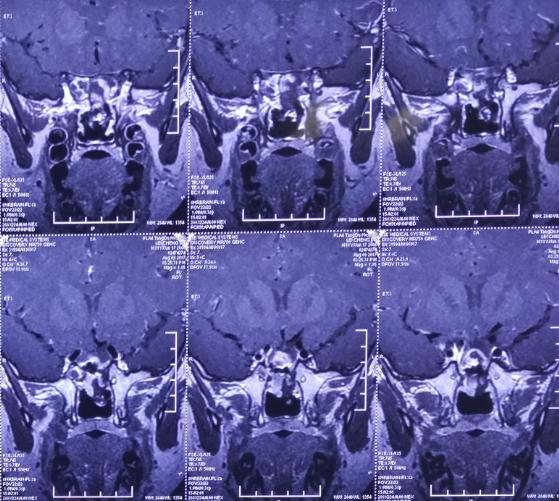

4、患者近期做头颅磁共振提示:鞍区占位性病变;

唐都医院小儿神经外科亚专业组组长王超博士结合患者病史、体征、影像学检查等诊断为先天性前颅底型颅裂,脑膜脑膨出建议及时手术。

影像资料